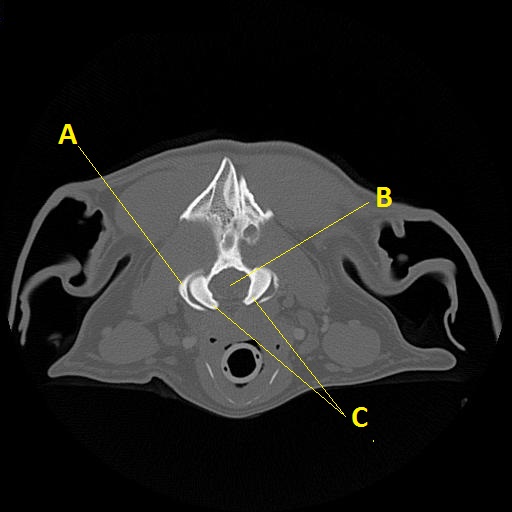

CT anatomy 13

Q. Identify the structures labeled below:

A.

A. cranial articular fovea of C1

B. foramen magnum

C. occipital condyles